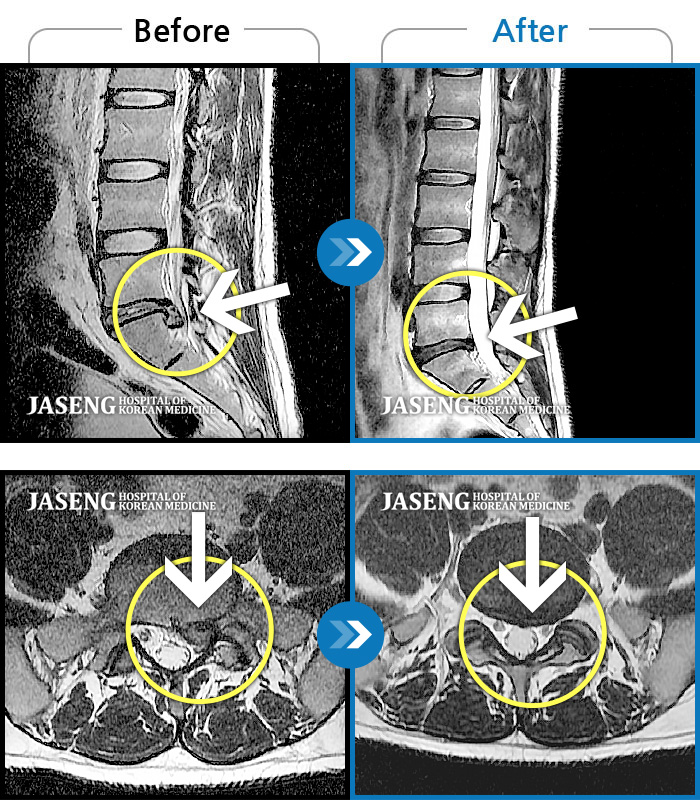

Before

After

환자에게 사전 동의를 받아 동일 조건에서 촬영되었습니다.

개인에 따라 치료 후 부작용이 발생할 수 있으니 의료진과 상담 후 치료를 진행하시기 바랍니다.

비수술치료를 위해 내원

우측 다리가 당겨서 걷기가 불편했다.